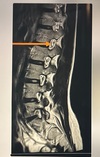

Which line points to the annulus fibrosis?

A